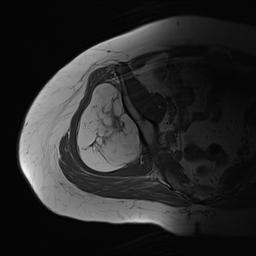

Liposarcoma posterior thigh

LS 3LS 2LS 1